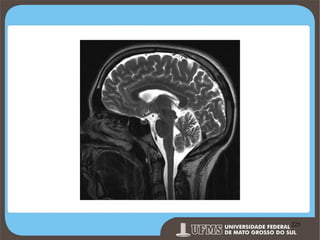

Figure 1. Sagittal T1-weighted image of the normal

brain showing typical flow of cerebrospinal fluid (CSF).